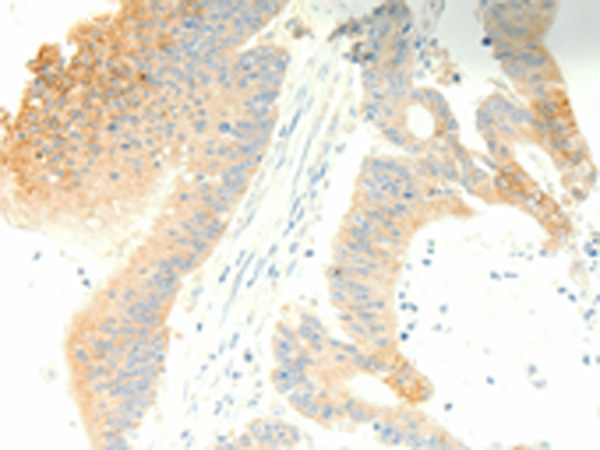

IHC positive control:

Human colon cancer and human thyroid cancer

IHC Recommend dilution:

25-100